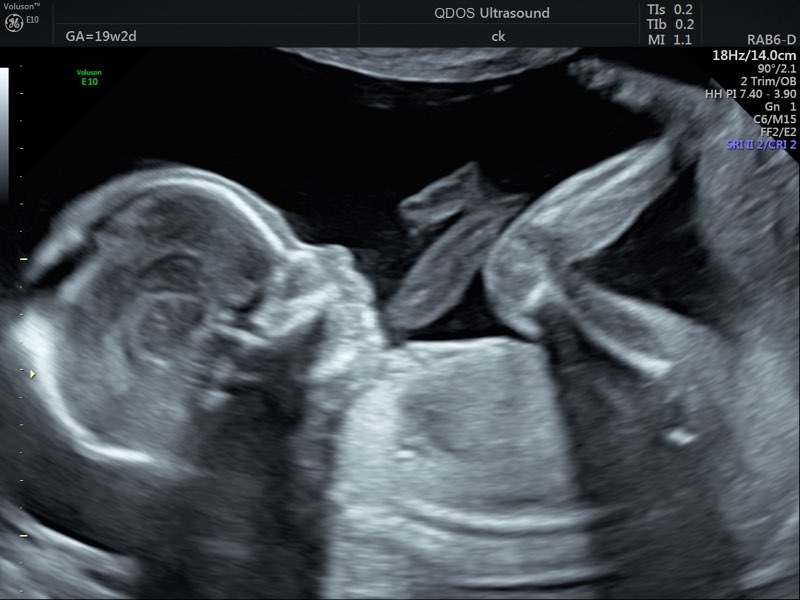

For many parents, the 19-21-week scan is an exciting milestone that offers reassurance about the healthy progress of the pregnancy. It’s also a rewarding moment, especially as the challenging early stages of pregnancy start to ease.

Seeing your baby move during the scan can be a comforting experience, particularly since you may not yet feel those movements, even though you might be asked about it frequently. By this stage, you might not have the same obvious symptoms to reassure you, so seeing your baby active on the screen can be a welcome reminder that everything is going well.